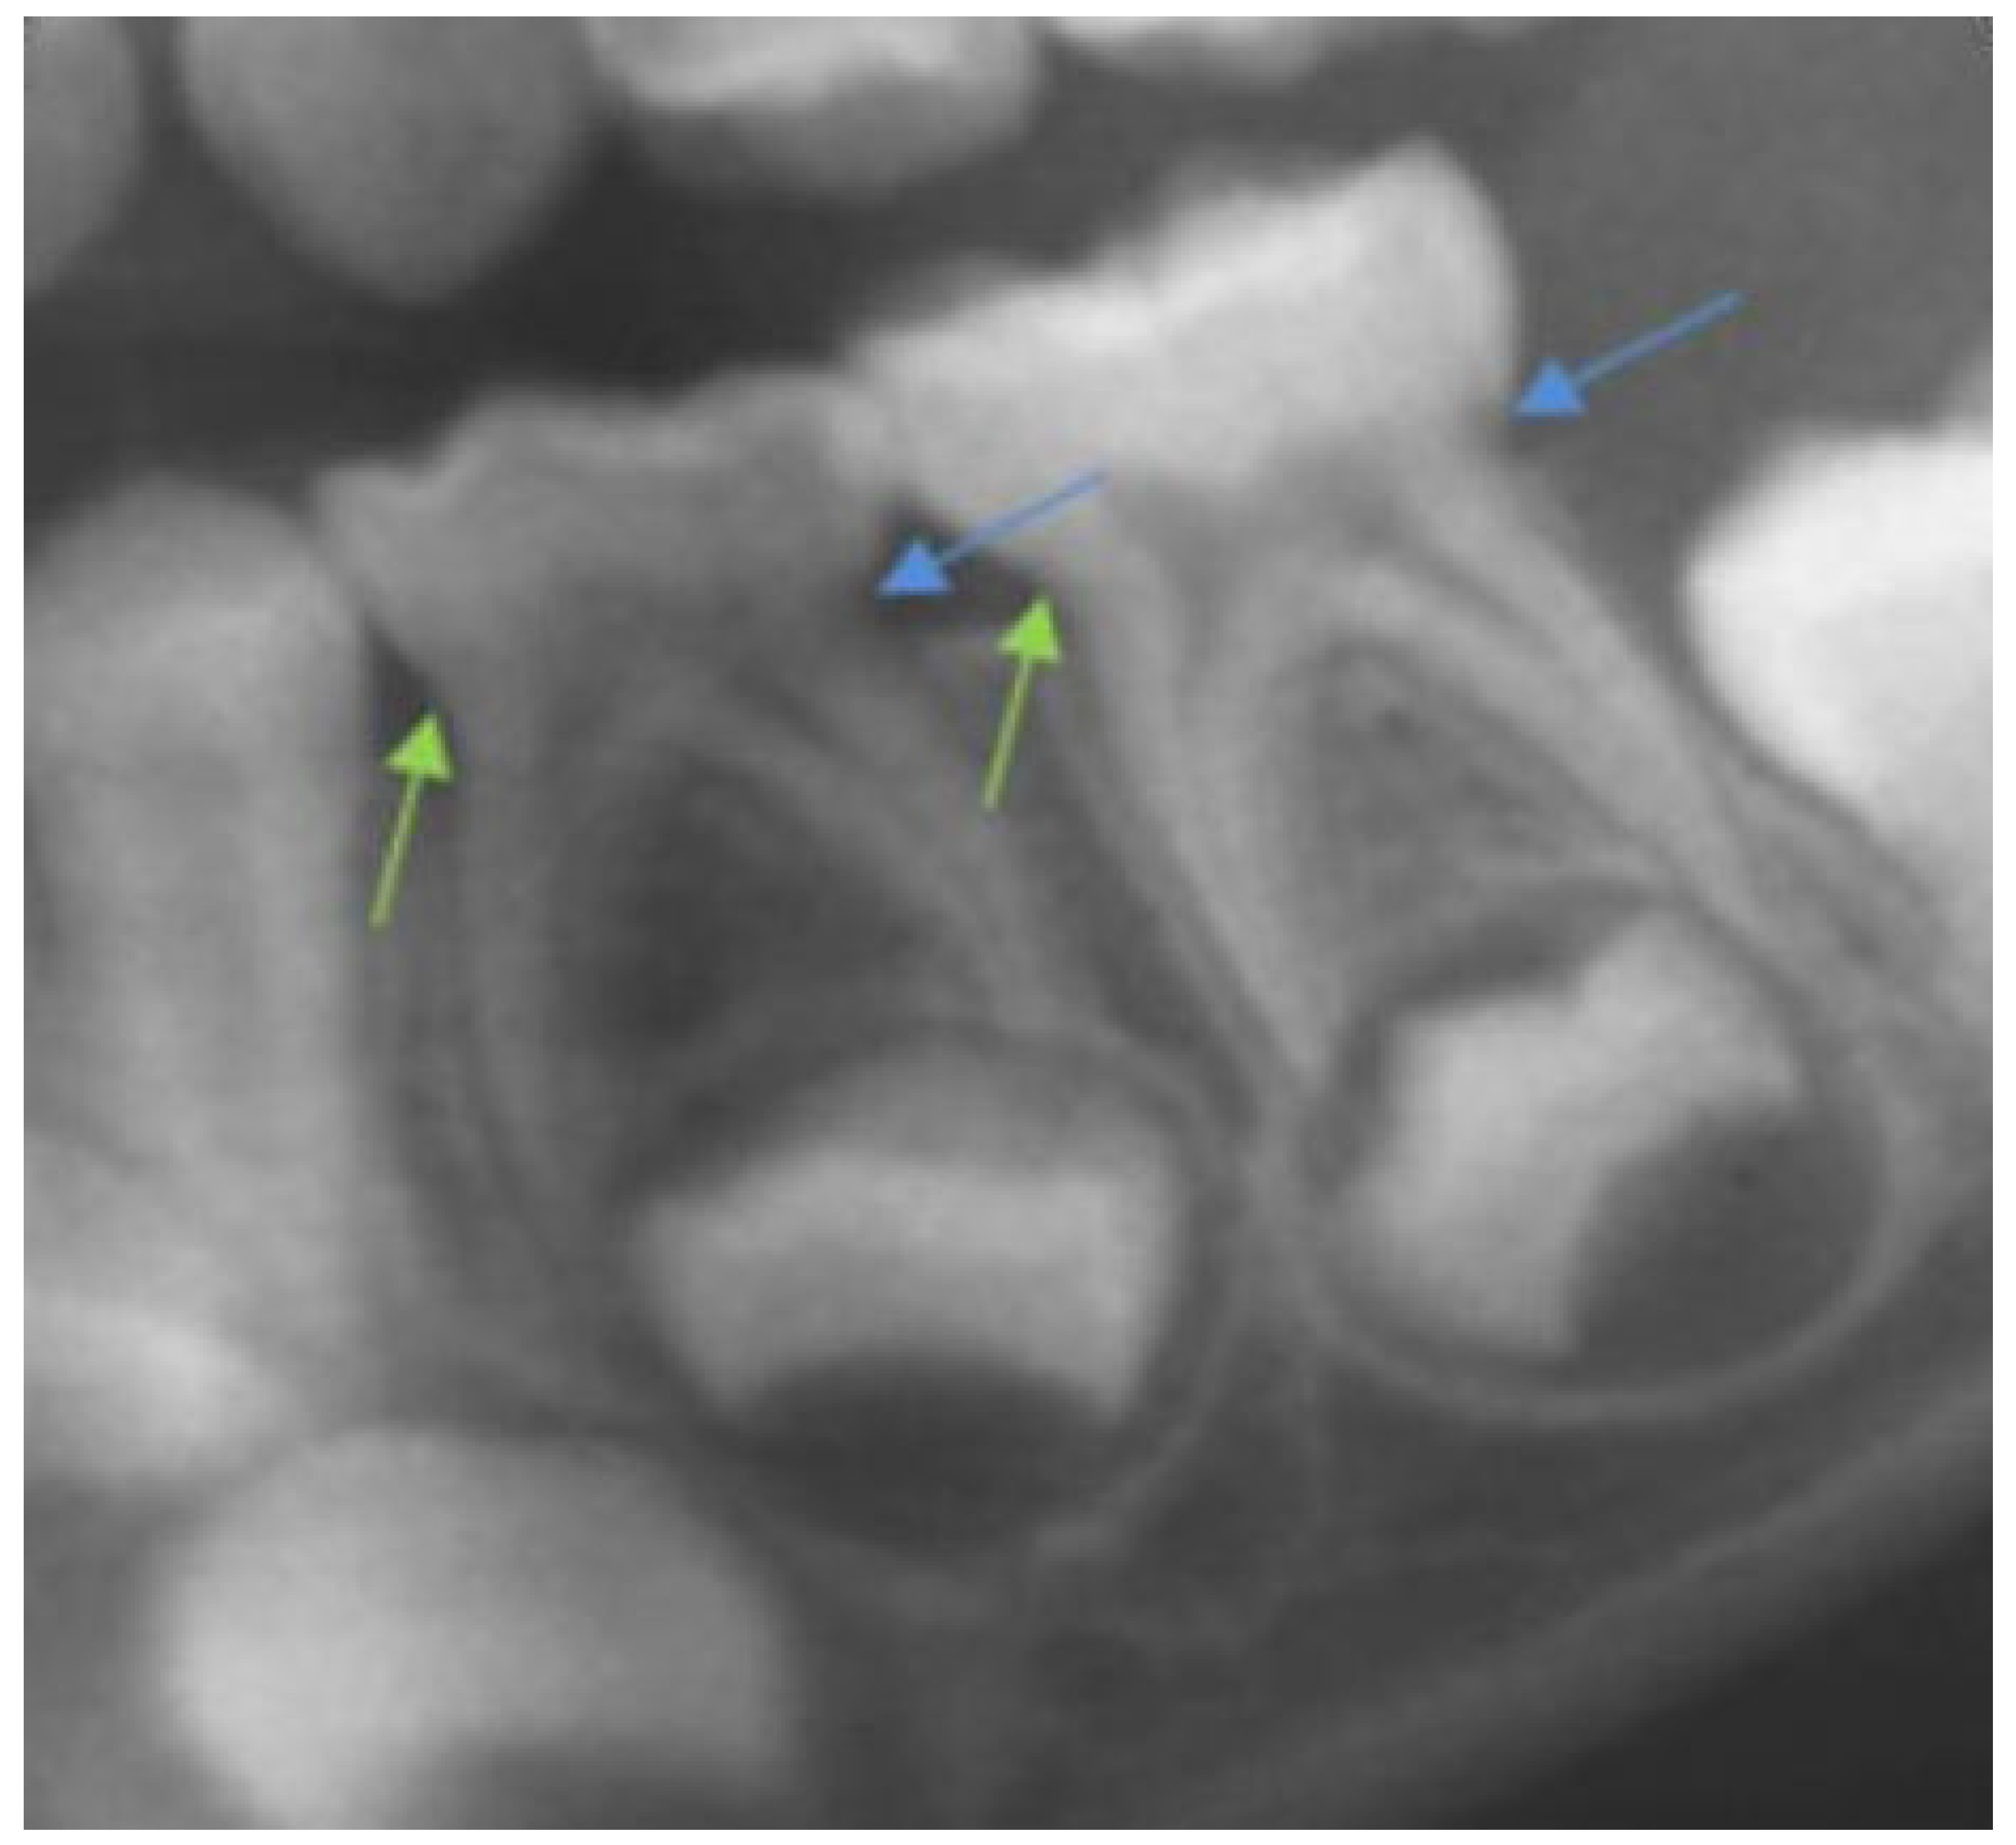

- Crown height was calculated as the distance between the line that links the mesial and distal cemento-enamel junctions and the highest point of the occlusal surface of the molar (Figure 1).

- Mesial root length was calculated as the distance between the mesial cemento-enamel junction and the most apical point of the mesial root.

- Distal radicular length was calculated in the same way as mesial root length, but in the distal molar area (Figure 1).

- Mesial and distal crown-to-root ratios (CRR-m and CRR-d, respectively) were calculated by dividing the length of each root by its coronal height.